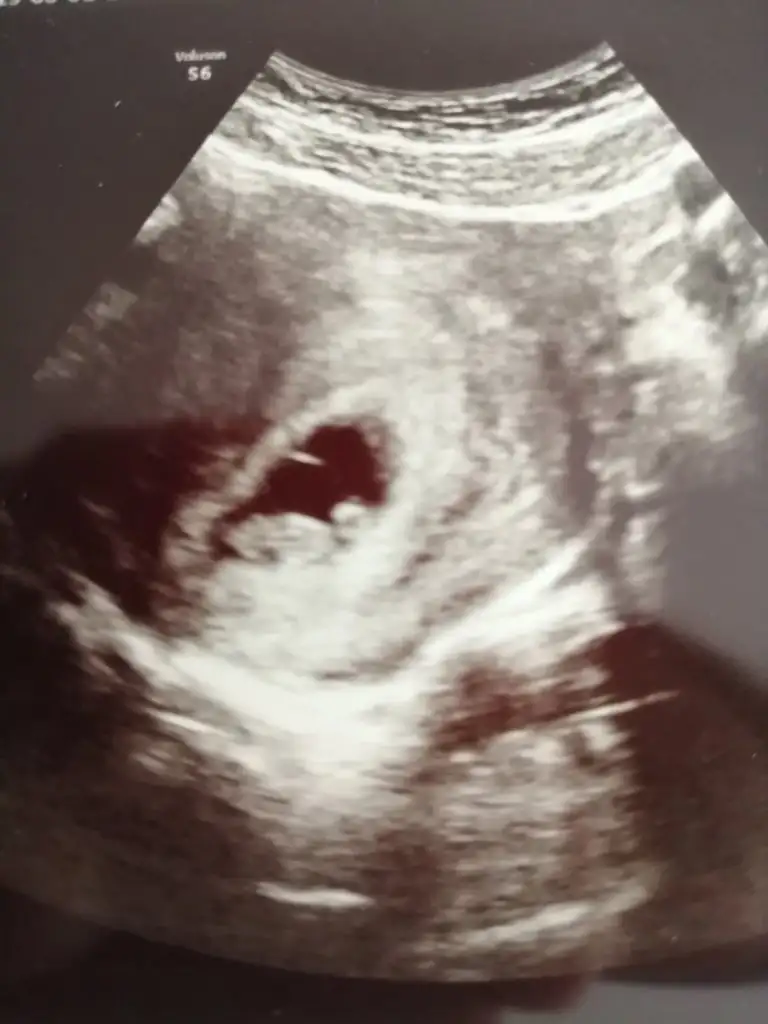

Pikolata banada plesentadan yorum yaparmisin cok rica etsem ilki 7 ikincisi 9 haftalik 2 side karindan usg6 veya 7 haftalık ultrason görüntüsü lazım. bir de karından mı yoksa vajinal mi ultrasonun belirtirsen sana da tahmin de bulunuruz.

Bu teoriye gore bebegin konumu onemli degil..plesentanin hangi tarafta oldugu onemli..plesenta nispeten daha parlak duruyo ultrason kagidinda ama bunu tespit etmek zor..

Hala buralardaysan canim banada plasentaya gore yorum yaparmisin 7 hafta ilki digeri 9 Hafta ikiside karindanKız cnm plasentayi net gördüm ama teori bu tabi tutar tutmaz